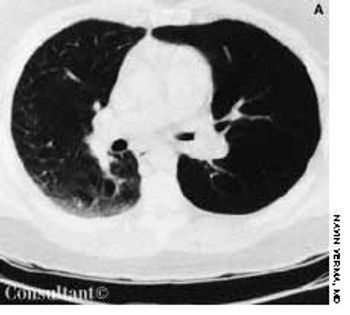

With a 1-year history of episodic wheezing, a 62-year-old woman (a smoker for the past 30 years) was being treated for bronchial asthma, but bronchodilator therapy did not control her symptoms. She was hospitalized with worsening dyspnea and a 4.5-kg (10-lb) weight loss over the past 3 months. There was no hemoptysis.